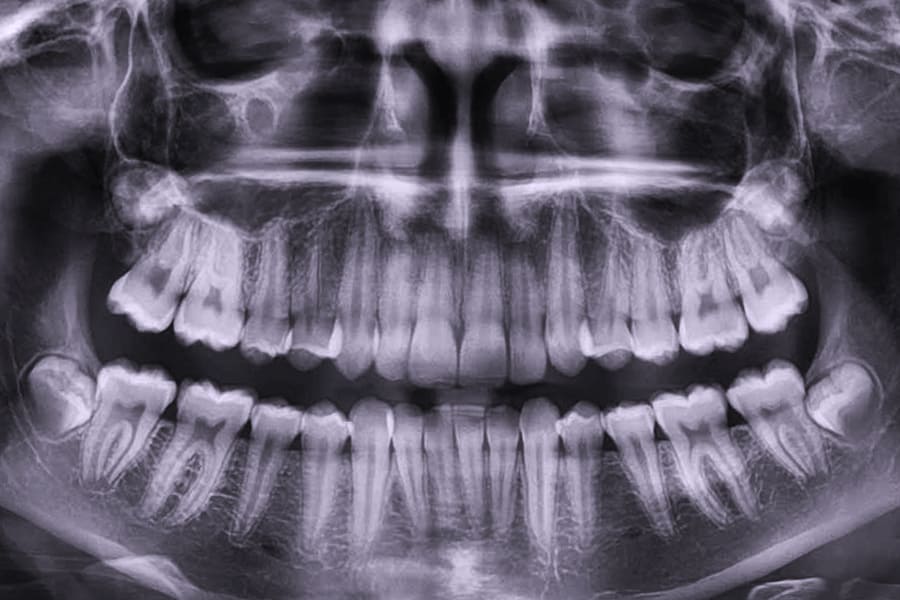

Панорама (ортопантомограмма, ОПТГ, панорамный снимок челюстей) – это обзорный круговой снимок зубов, при котором видна вся челюсть, развернутая в двухмерной плоскости. Она может быть цифровой и пленочной.

Панорамный снимок (или ортопантомограмма) – это плоское двухмерное изображение челюстей, зубов, гайморовых пазух и даже височно-нижнечелюстного сустава. Поскольку поверхность челюстей изогнутая, на плоской рентгеновской плёнке снимок отображается неравномерно увеличенным в боковых и передних отделах челюстей – то есть слегка деформированым.

- Много информации на одном снимке — видны все зубы с корнями, обе челюсти, гайморовы пазухи, височно-нижнечелюстные суставы, частично даже полость носа.

Панорамный снимок челюсти позволяет стоматологу получить изображение сразу всех зубов, включая верхнечелюстные суставы.

На рентгене отображаются зубные каналы, корни, костная ткань, пломбы и импланты.